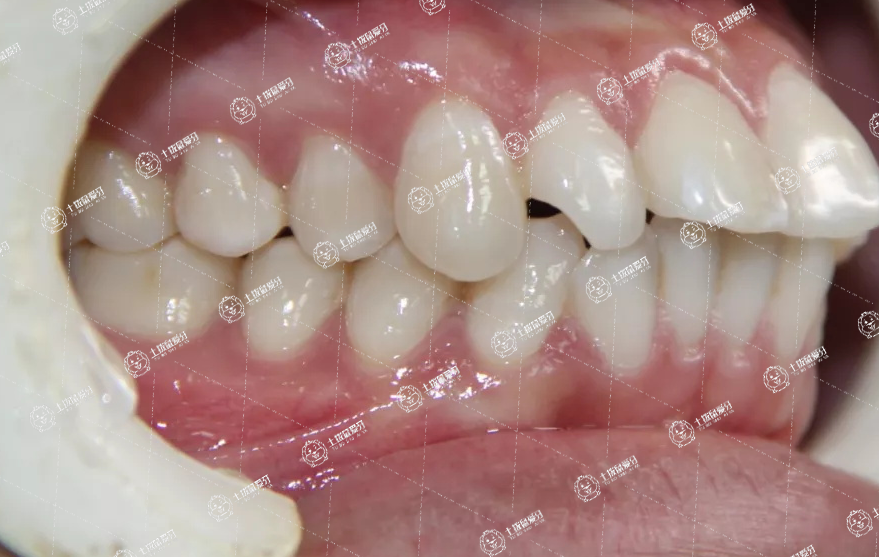

看到各種牙齒不整齊影響顏值的情況,其中牙齒前突算是相當影響顏值的一種牙齒畸形情況。一般患者上排牙齒前突后往往就會導致自然狀態(tài)下嘴巴不能閉攏,牙齒暴露在外面,看起來相當影響雅觀。目前解決牙齒前突最好的辦法是做牙齒矯正,上排牙齒前突矯正多少錢?對于牙友們比較關注的這一問題,接下來,我們一起來了解一下。

上排牙齒前突矯正多少錢關鍵與牙齒前突的水平、矯治方法等相關,稍微前突能夠采取全瓷貼面的方法修整,做前排牙齒凸起矯正一般應該到正規(guī)的牙科醫(yī)院門診,在??漆t(yī)生的引導下選擇矯正,防止對牙齒導致?lián)p傷。

上牙齒前突矯正約需1000-10萬元。前牙輕度突出時,可以磨除部分釉質(zhì),制作全瓷貼面修復,約需2000-4000元。前牙中度突出時,可以粘固樁核,調(diào)整牙體長軸方向,制作烤瓷或全瓷牙冠修復,約需600-5000元。前突造成開唇露齒時,可以佩戴固定或隱形矯治器,內(nèi)收前牙,壓低臨床牙冠,改變突度,約需1-5萬元。發(fā)生骨性前突時,可以進行正頜外科手術(shù),磨除過多的牙槽骨,約需8-10萬元。矯治結(jié)束后,要佩戴保持器,限制牙齒移位。